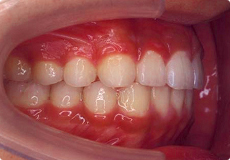

よい歯並びの例

矯正治療では、このような咬み合わせを獲得することが目標の一つとなります。

お口の中には、親知らずを除くと上下で28本の歯がはえます。

隙間や凸凹などもなく、アーチ状にきれいに並んでいます。

上下の真ん中が一致しています。

よい咬み合わせでは、前歯は上の歯が下の歯より2mmくらい前へ出て、同じく2mmくらい重なります。奥歯は、歯の山と谷が歯車のようにしっかり咬み合います。